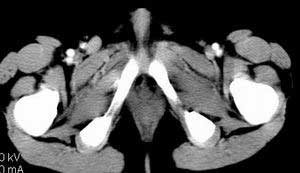

| 患者,男,9岁,因右下腹包块入院,血象不高,不规则发热,常超40度。 平扫: ![]() ![]() ![]() ![]() ![]() ![]() ![]() ![]() ![]() ![]() ![]() ![]() ![]() ![]() ![]() ![]() ![]() ![]() 增强: ![]() ![]() ![]() ![]() ![]() ![]() ![]() ![]() ![]() ![]() ![]() ![]() ![]() ![]() jiajie发言:骶椎右前区不规则软组织肿块,边缘光整,密度均匀,增强后均匀强化,右腹股沟区可见肿大淋巴结,临床有时发热,考虑淋巴瘤,儿童盆腔肿瘤应与神经母细胞瘤和横纹肌肉瘤鉴别。 longzhanghui发言:印象:盆腔右后壁不规则软组织肿块,并向前延伸.似为多个肿块融合,呈中等强化.初步考虑淋巴瘤. 听蝉观竹发言:右侧髂内、外组淋巴结肿大,从其形态和融合的情况看,同意大家意见-----考虑恶性病变,但是9岁男孩还要注意检查睾丸情况,有无隐睾? 常常类似情况是隐睾发生精原细胞瘤淋巴结转移,这个病例也要注意这一点!!! 广东凌发言:大家好,在这里我想说一下个人观点,我建议上传图片的同志能否辛苦一点就是把病史和图片都上传完整一点,比如这个病人的腹膜窗,并且这个病人的肠道的准备也是不怎么好,就从现有的质料看:病灶属于淋巴结肿大当无大的争议,有融合趋势,其内无坏死,边缘强化为主,故考虑:淋巴瘤!建议用腹膜窗看一下和肠道的关系! 阿圣发言:病灶属于淋巴结肿大当无大的争议,有融合趋势,其内无坏死,边缘强化为主,故考虑:淋巴瘤 结果是:淋巴瘤 病例来源:ct762。由宁静致远发布: http://www.radinet.com.cn/forum_view.asp?forum_id=4&view_id=2182 |